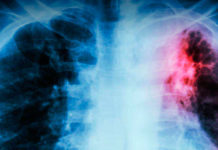

La tuberculosis resiste desde la prehistoria y se cobra 700 vidas al año en...

Descripta por Hipócrates en la Antigua Grecia, en la...